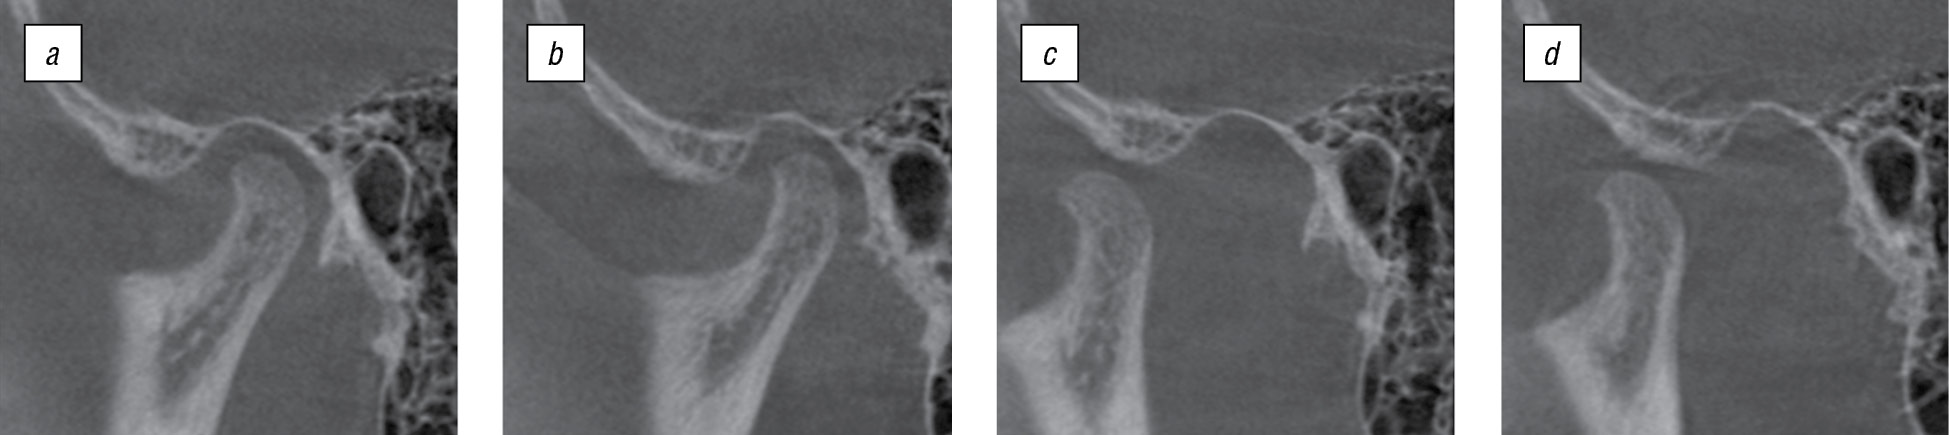

При данной аномалии прикуса возможны нарушения взаимоотношения костных элементов ВНЧС, такие как дистальное (заднее) смещение головок нижней челюсти и сужение заднего отдела суставной щели. В связи с этим была проведена КЛКТ ВНЧС (рис. 5).

Рис. 5. Конусно-лучевая компьютерная томограмма височно-нижнечелюстного сустава пациента П., 15 лет: a — при закрытом рте справа: b — при закрытом рте слева; c — при открытом рте справа; d — при открытом рте слева / Fig. 5. Cone-beam computed tomogram of the temporomandibular joint of patient P., 15 years old: a — with the closed mouth on the right; b — with the closed mouth on the left; c — with the open mouth on the right; d — with the open mouth on the left

Результаты измерения размера суставной щели ВНЧС по методике Н.А. Рабухиной (рис. 6) представлены в табл. 1.

По данным КЛКТ в заднем отделе обнаружено сужение суставной щели справа и слева. В положении привычной окклюзии головки нижней челюсти смещены дистально. При открытом рте суставные головки располагаются на вершине суставных бугорков, что соответствует норме. Анализ угловых параметров, проведенный в программе «Краниометрия», показал отклонения в соотношении костных элементов ВНЧС. Для правого ВНЧС угол α — 8,2°, угол β — 7,688°, угол γ — 164,11°; для левого — 4,399°, 4,127°, 171,47° соответственно. Также была выявлена асимметрия в расположении суставных элементов между правым и левым ВНЧС (рис. 7).

Рис. 7. Анализ угловых параметров, показывающих соотношение костных элементов височно-нижнечелюстного сустава, выполненный в программе «Краниометрия», пациента П., 15 лет: а — при закрытом рте справа; b — при закрытом рте слева / Fig. 7. Analysis of the angular parameters showing the ratio of bone elements of the temporomandibular joint, performed in the “Craniometry” program, patient P., 15 years old: a — with the closed mouth on the right; b — with the closed mouth on the left

После проведенного исследования был поставлен уточненный диагноз: дистальная окклюзия, гнатическая форма, сужение заднего отдела суставной щели ВНЧС, дистальное смещение головок нижней челюсти.